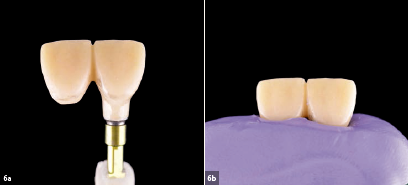

Εικ. 6a&b

Κατασκευή του εξατομικευμένου άξονα αποτύπωσης για το εμφύτευμα στην περιοχή του 11. Το προφίλ ανάδυσης της προσωρινής αποκατάστασης θα πρέπει να μεταφερθεί στη μόνιμη αποκατάσταση. Αυτή η διαδικασία προλαμβάνει την κατάρρευση του προφίλ ανάδυσης κατά τη λήψη αποτυπώματος.